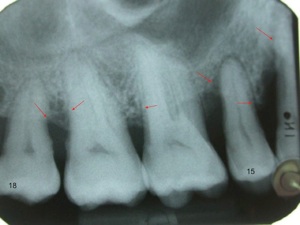

L’atteinte de la furcation interradiculaire est un facteur aggravant.

Résorption osseuse interradiculaire, classification des furcations:

Parodontite = perte d’attache ( os , gencive, ligaments , cément radiculaire) , partiellement réversible par traitement non chirurgical ( détartrages et surfaçages radiculaires ) ou chirurgical et reprise correcte de l'hygiène dentaire et maintenance parodontale régulière . La perte osseuse horizontale est irréversible. On peut régénérer l’os partiellement dans le cas des lésions osseuses verticales.

En fonction de la profondeur des poches parodontales on décide du type de traitement :

1.moins de 5 mm = non chirurgical ( détartrages et surfaçages radiculaires )

2.plus de 5 mm = chirurgical